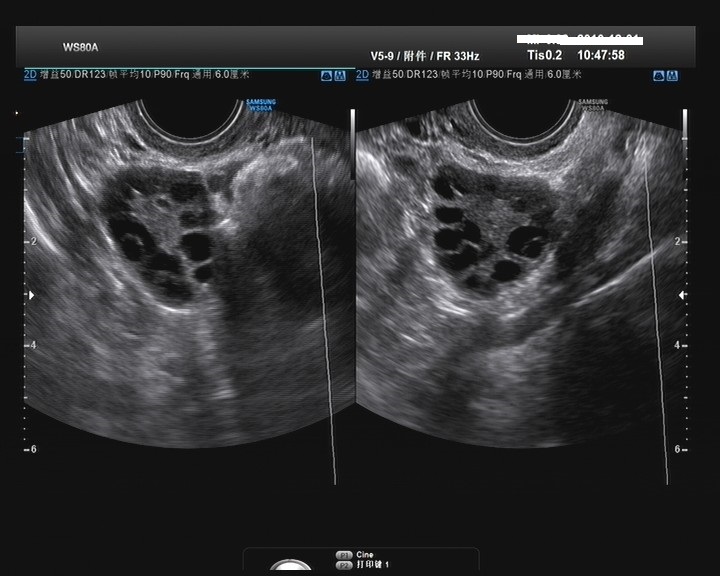

生殖科医生详细询问了小叶的病史,简单查体,并开了几项检查,妇科激素六项、空腹血糖及胰岛素以及经阴道B超。根据结果最后对小叶进行了诊断:多囊卵巢综合征PCOS。

多囊卵巢综合征是育龄期女性最常见的生殖内分泌疾病,是引起无排卵不孕和高雄激素血症的主要原因,其发病率高达5%-10%。病因学研究发现,PCOS的复杂临床表现和生化特征是遗传因素和环境因素共同作用的结果。多囊卵巢综合征具有明显的家族聚集性。PCOS的主要临床表现为:月经稀发或闭经、不孕、高雄激素征、卵巢多囊样表现。内分泌及代谢异常表现在血浆促黄体生成素LH水平增高,促黄体生成素/卵泡刺激素(LH/FSH)值增高、高胰岛素血症、胰岛素抵抗、肥胖以及异常脂质血症等。